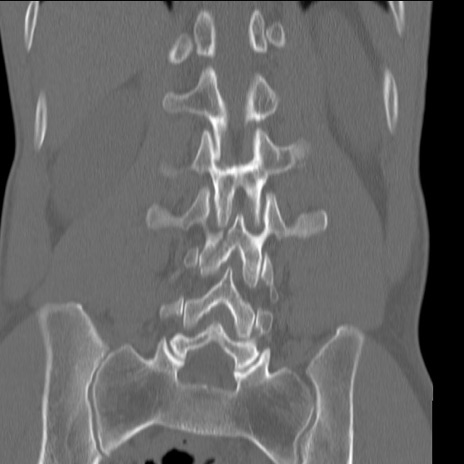

症例3 腰椎CT(冠状断像)

腰椎CT

矢状断像